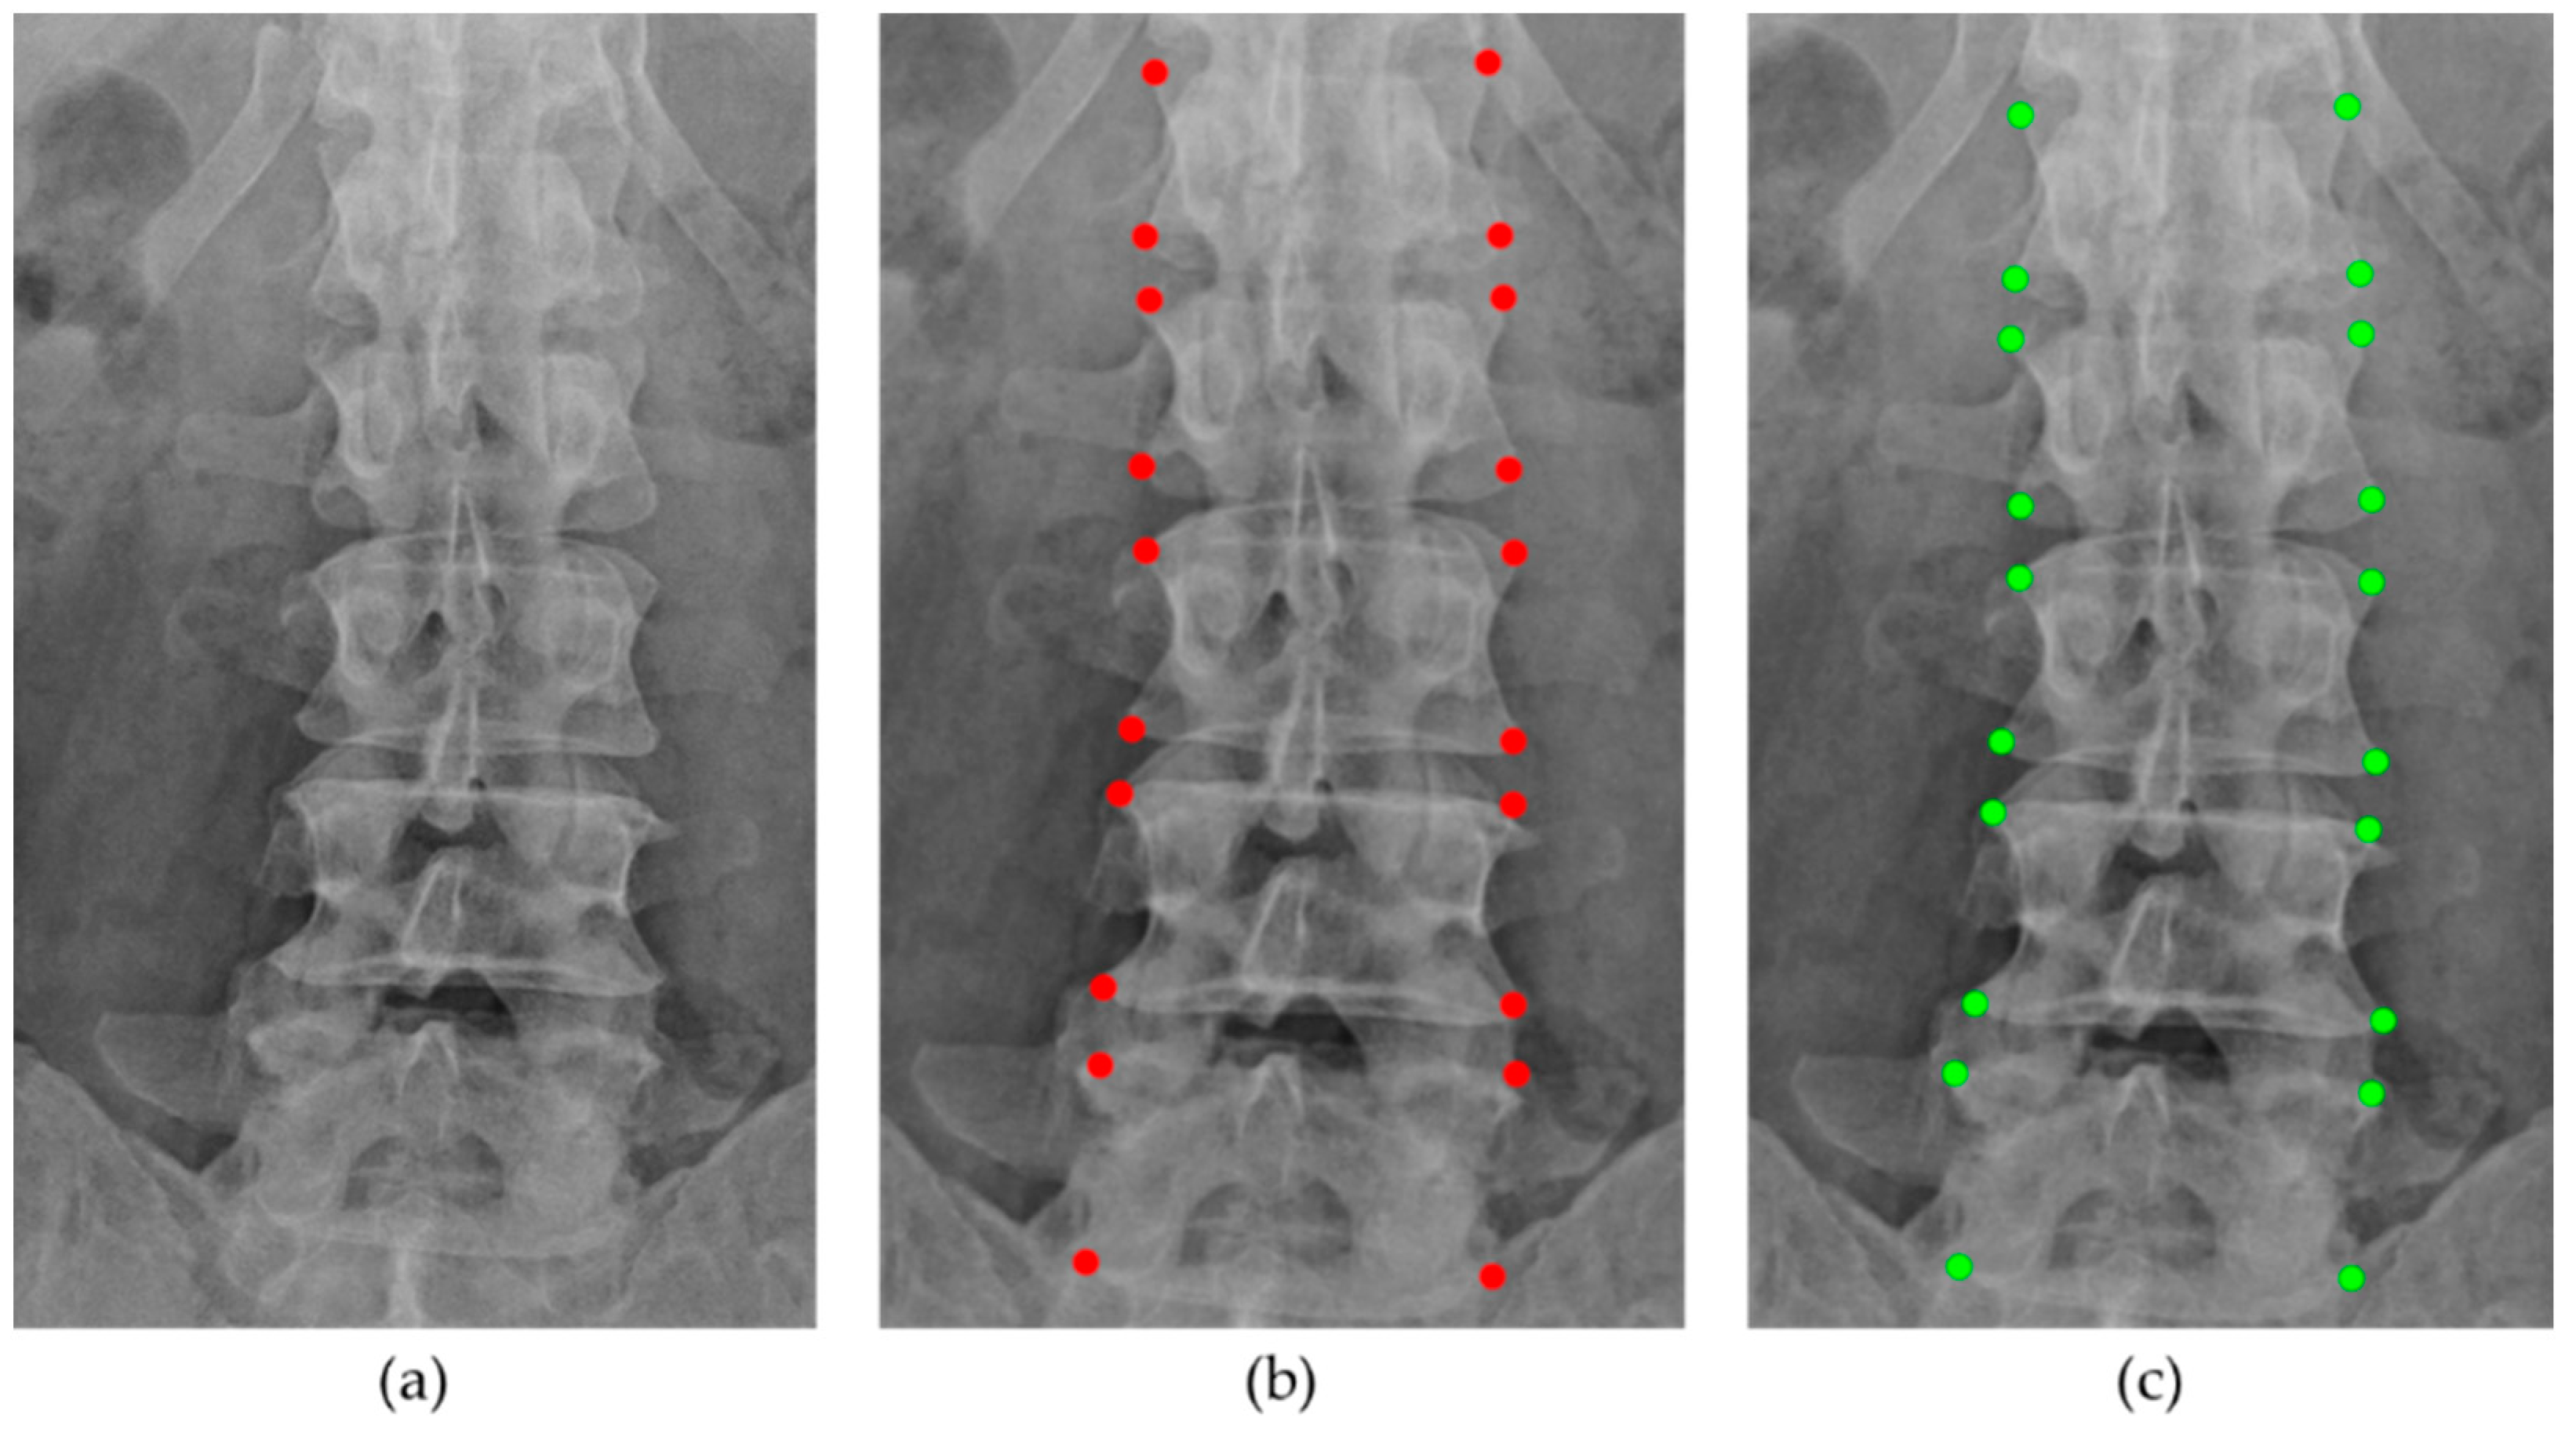

2.2.1. Vertebral Positions

2.4.2. Vertebral Corner Points Extraction

3.2. Vertebral Corner Point Extraction